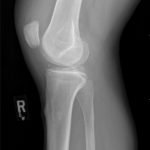

Radiographs of the knee showed multiple radio-dense lines paralleling the articular surface (see red arrows) consistent with calcium pyrophosphate crystal deposition within the joint often seen in calcium pyrophosphate disease (CPPD) also known as pseudogout.

Patients commonly present to the emergency department with non-traumatic joint pain. Arthrocentesis is an important diagnostic tool to evaluate for septic arthritis, gout, or pseudogout. Arthrocentesis can demonstrate crystals or abnormal cell count, gram stain, and culture.[1] In the evaluation of joint pain, plain films are usually obtained to evaluate for fracture, dislocation, effusion, or secondary signs of infection. In this case the classic x-ray supported the diagnosis of CPPD.2 The patient was found to have positively birefringent rhomboid shaped crystals consistent with pseudogout on arthrocentesis. Gram stain and culture were both negative. The patient was discharged with NSAIDs and had significant improvement in symptoms upon follow up with primary care physician in 3 days.